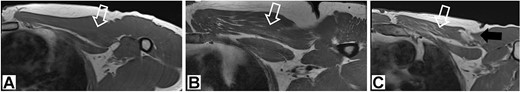

In this study, we presented a prospective comparative study of 40 patients underwent anatomical reconstruction of the PMM tendon using autologous fascia lata graft or autologous hamstring graft [15, 16, 22]. All patients have presented chronically ruptured muscles (Fig. 1) and were evaluated with MRI (Fig. 2) before the surgery. All patients underwent histological evaluation of the pectoralis tendon in a biopsy took during the repair surgery (Fig. 3).

1.5 T T1 magnetic resonance image showing chronic aspects within the pectoralis major muscle.

Magnetic resonance image of the affected muscle

We performed MRI image analysis in 20 patients underwent surgical treatment. Those patients were randomized from all surgical patients in a ration of 2:1 with 10 non-weightlifting athletes’ controls. We used MRI to assess muscle degeneration prior to surgery using a protocol designed for PMM evaluations. For this randomization we used randomizer.org in a simple way. All patients evaluated with MRI had histological evaluation also. All MRI were performed using the same 1.5 T MRI machine (Siemens, Erlangen, Germany); the parameters are provided in Table 1 and degeneration evaluation in Table 2.

Additionally, no significant differences were found between the operated and non-operated sides of the participants in the control group regarding the muscle degeneration measurements (Table 6) Figs 2–4 or the PMM MRI protocol, i.e. the largest PMM area (P = 0.251), PMM volume (P > 0.999), and humeral PMM insertion area (P = 0.136).